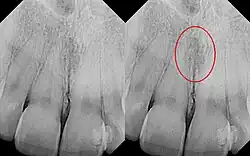

| Identical images with heart-shaped radiolucency highlighted in right film. | |

The nasopalatine duct cyst (NPDC) occurs in the median of the palate, usually anterior to first molars. It often appears between the roots of the maxillary central incisors. Radiographically, it may often appear as a heart-shaped radiolucency. It is usually asymptomatic, but may sometimes produce an elevation in the anterior portion of the palate. It was first described by Meyer in 1914.[1]

As a cyst, the nasopalatine duct cyst requires histological analysis for a definitive diagnosis. Radiographically, the nasopalatine cyst appears as a well-demarcated round, ovoid, or heart-shaped structure presenting in the midline of the maxilla.[6]